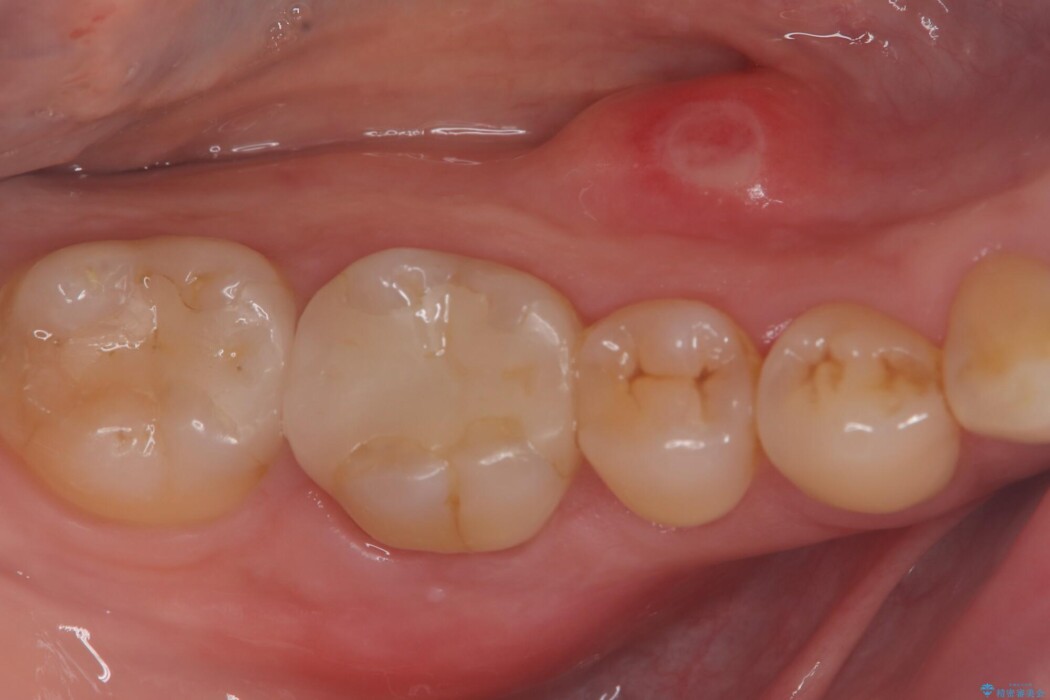

右下奥歯(6番)の激しい痛みと、歯ぐきの腫れを主訴にご来院されました。

術後の経過は非常に良く、あんなに大きかった膿の袋は消え、健康な骨が再生しているのが確認できました。痛みや腫れも消えて抜歯を免れ、現在は被せ物を入れてしっかりお食事を楽しんでいただけるようになっています。